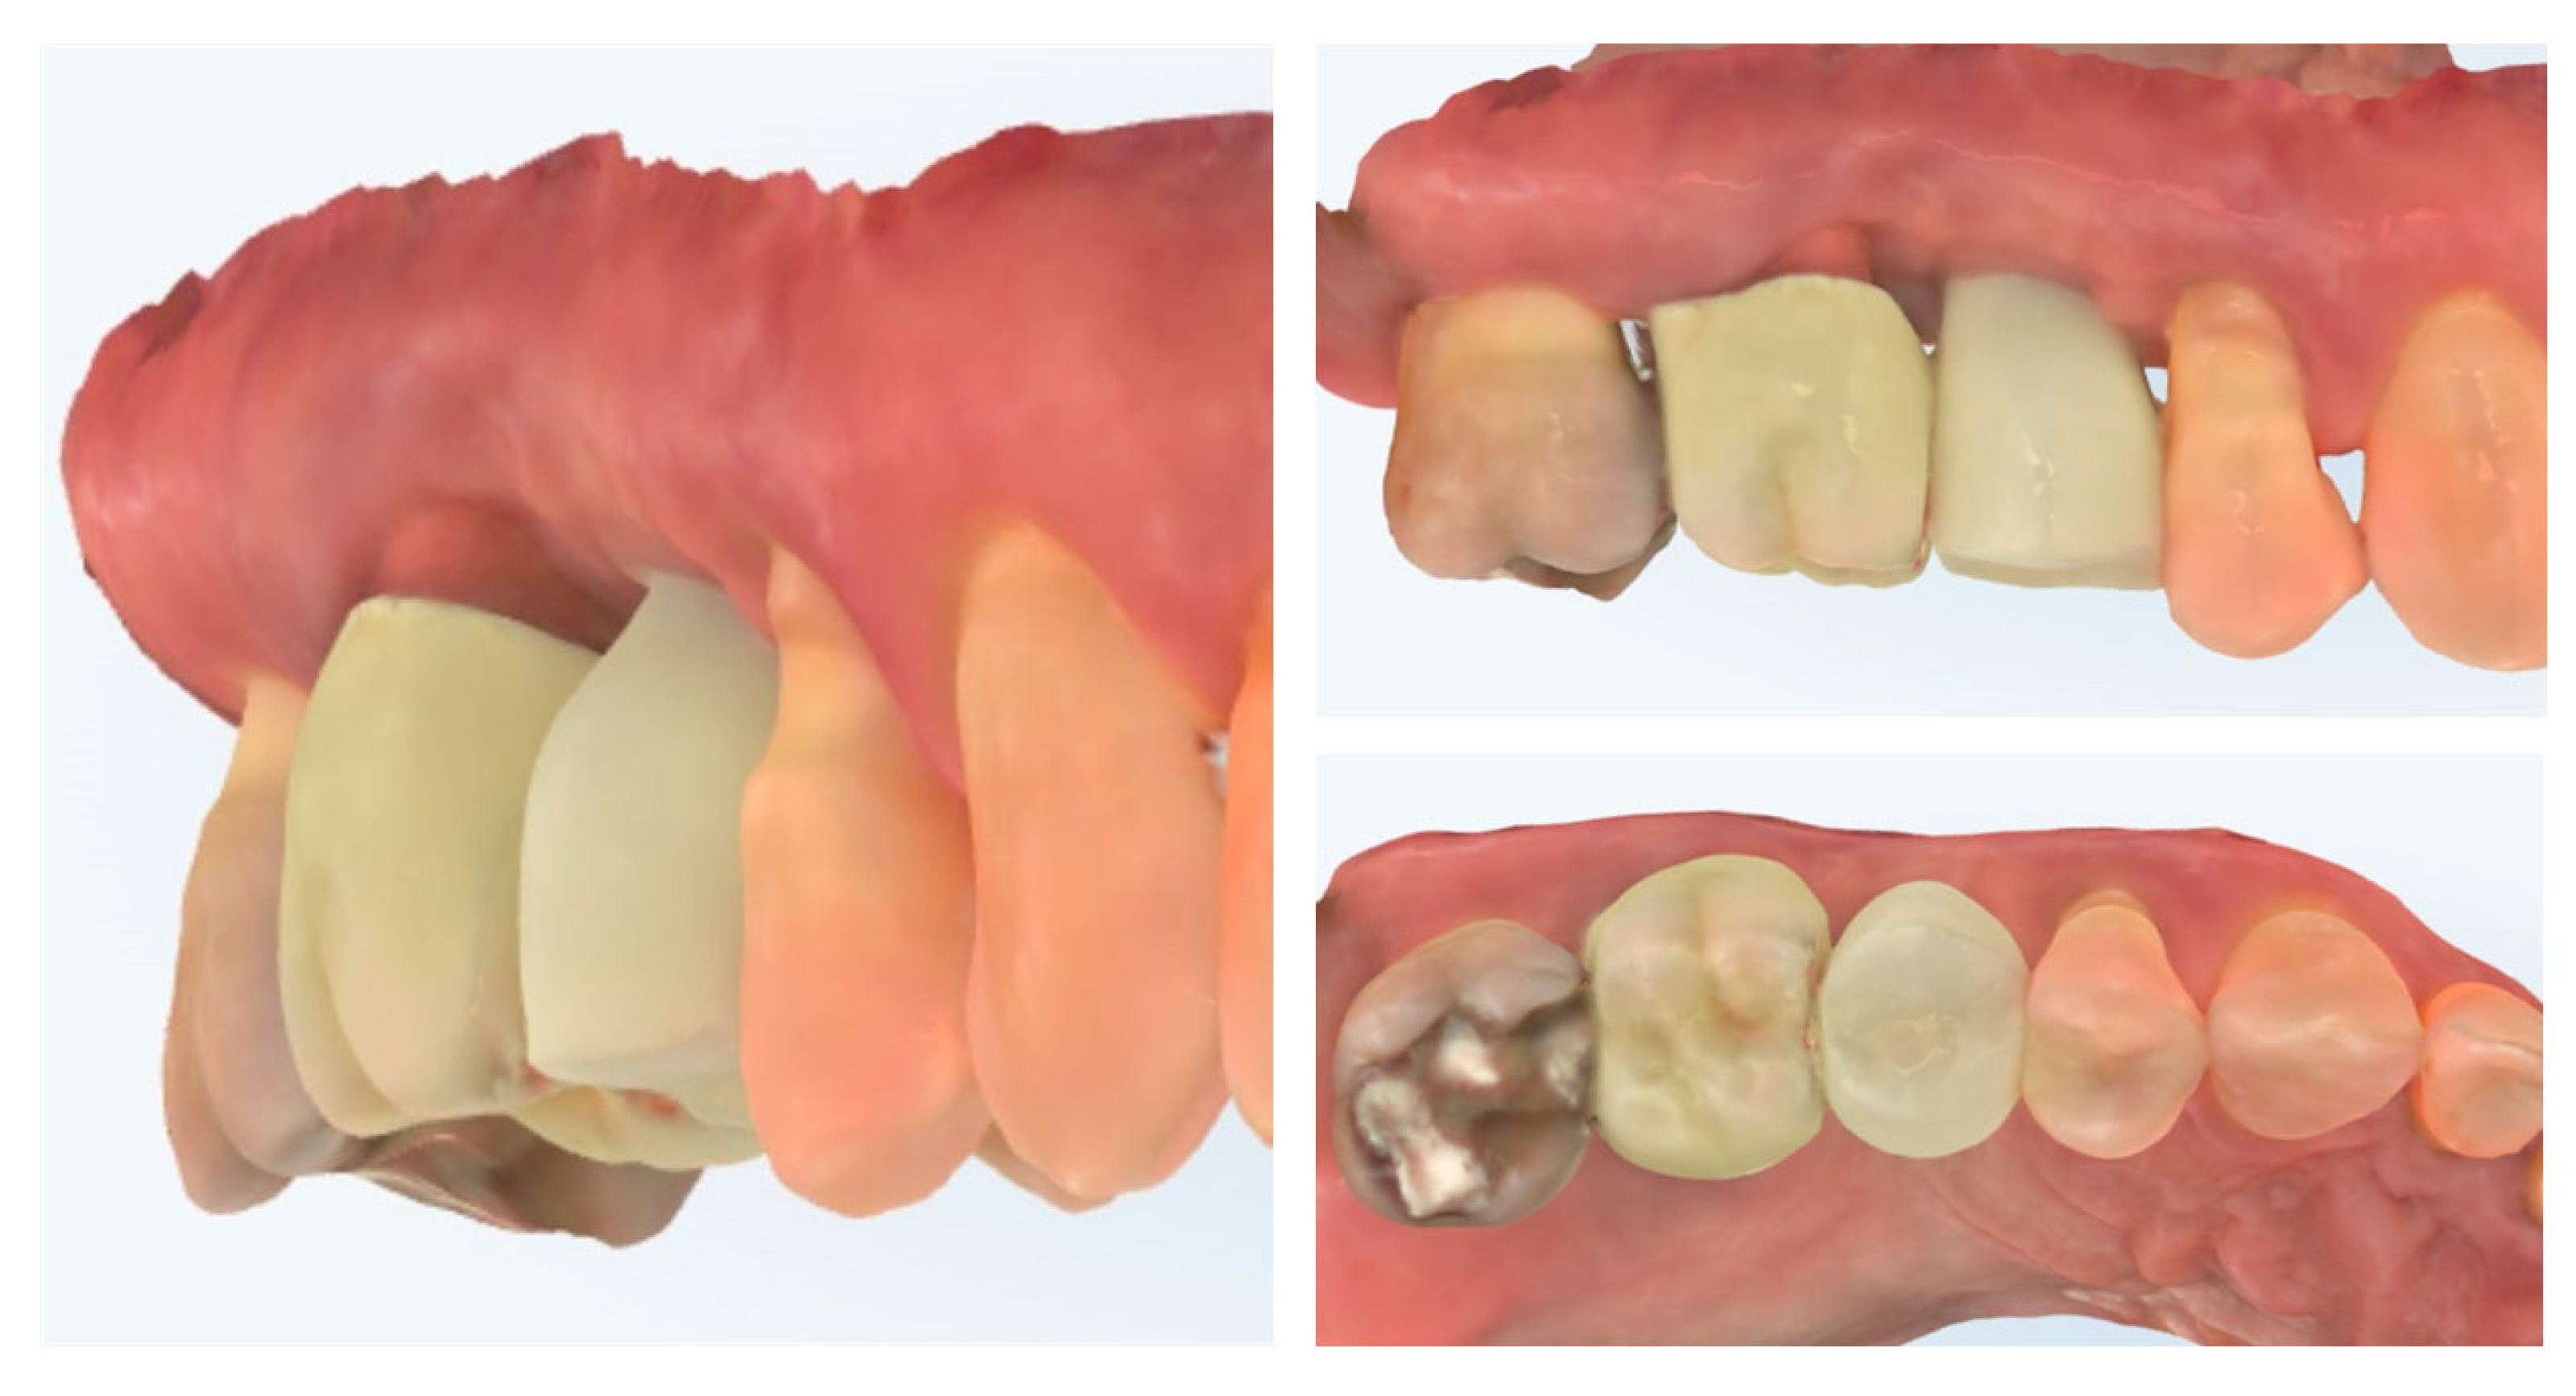

Clinical view at 6 months following delivery of the definitive prosthetic restorations demonstrates stable peri-implant and periodontal soft tissues (Figure 18). The mucosal margin is healthy, with adequate buccal thickness and harmonious integration of the implant-supported crown in region 15 and the adjacent tooth-supported crown in region 16. No signs of inflammation, mucosal recession, or soft tissue collapse are evident, confirming long-term stability of the roll flap augmentation and successful functional and esthetic rehabilitation. The X-ray control shows stable crestal bone levels.

Figure 18.

Clinical appearance and X-ray control 6 months after definitive prosthetic treatment (14 months post-op).

The comparison of the X-rays shown in Figure 19 presents the stability of the crestal bone levels prior to implant placement to the 14th month after implantation. The combination from minimally invasive implant site preparation, provision of an adequate peri-implant soft tissue thickness, and proper emergence profile of the implant-supported restoration ensured the protection of the bone volume without signs of remodelling or resorption.

Figure 19.

Stability of the crestal peri-implant bone.

Figure 20 shows the dynamic of soft tissue maturation and development. The combination from soft tissue augmentation procedure with the modified roll flap and soft tissue conditioning with the temporary crown led to complete resolution of the horizontal defect of the alveolar crest and provided adequate soft tissue thickness for long-term stability of the implant-supported restoration.

Figure 20.

Dynamic of soft tissue maturation and development.